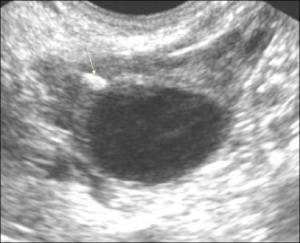

При ультразвуковом обследовании гиперэхогенные включения выглядят как белые пятна, которые являются лишними элементами в структуре почки. Врач может определить наличие или отсутствие акустической тени, что помогает оценить плотность гиперэхогенного включения.

В ходе ультразвукового исследования врач-диагност может обнаружить эхоплотные структуры, которые на экране выглядят как светлые, почти белые пятна. Оборудование позволяет различать эти объекты по наличию акустической тени, которая возникает, когда участок настолько плотен, что не пропускает звуковую волну.

Гиперэхогенные включения делятся на три группы в зависимости от их визуализации и наличия акустической тени:

-

Значительные по размеру образования с акустической тенью. Это характерно для камней и макрокальцификатов. Иногда так выглядят участки склероза (соединительная ткань, заменившая функциональную в результате некроза) или гематомы (кровоизлияния в ткани почки), где со временем накопилось много кальцификатов.

Крупные умеренно плотные включения без акустической тени. Это могут быть доброкачественные новообразования – фибромы, онкоцитомы, гемангиомы, а также заполненные жидкостью полости – плотные кисты. Склерозированные участки тканей и скопления очень мелких почечных камней (песка) также могут иметь среднюю плотность, как и зоны абсцесса.

Мелкие вкрапления белого цвета, которые выглядят как светящиеся точки. Это могут быть мелкие, но плотные кальцификаты или псаммомные тела – округлые образования размером до 3 мм с слоистой структурой, состоящие из белково-липидных комплексов. Эти включения по плотности превосходят любую ткань организма, и их наличие в почках может указывать на злокачественное новообразование.